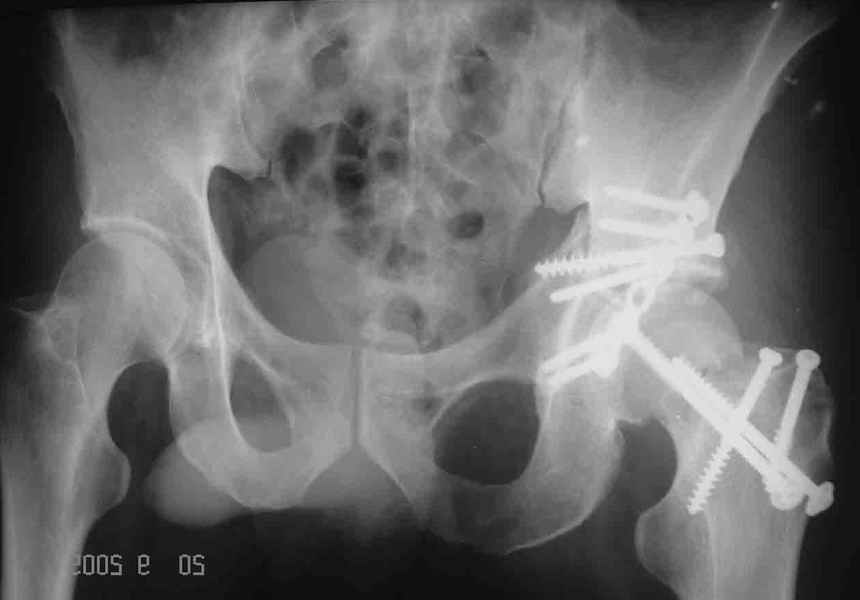

Послеоперационный снимок прямой 5/05/03

Больной 18 мая 2003 года в автоаварии получил перелом левой вертлужной впадины, вывих бедра. Госпитализирован в один из стационаров области.Вывих вправлен. В последствии бедро вывихивалось еще дважды. На консультацию был представлен снимок от 19.05.03г., больной переведен к нам 3.06.03г. Снимок при поступлении - перелом впадины, задне-верхний вывих бедра. 05.06.2003 г. выполнено открытое вправление вывиха левого бедра и остеосинтез стенки вертлужной впадины двумя винтами. Послеоперационный период без осложнений. Объем движений в левом тазобедренном суставе восстановился полностью. Выписан на амбулаторное лечение в удовлетворительном состоянии с рекомендациями 3 месяца ходить на костылях без нагрузки на оперированную конечность. На контрольных рентгенограммах левого тазобедренного сустава 13.10.2003 г. - признаки консолидации перелома; плотность, форма головки и состояние суставных поверхностей удовлетворительные. Разрешена дозированная осевая нагрузка, на конечность с использованием дополнительной опоры. 19.12.2003 г. больной обратился с жалобами на боли в левом тазобедренном суставе. На рентгенограммах левого тазобедренного сустава 19.12.2003 г., 20.02.04г. - асептичекий некроз головки бедра. 5.04.04г. - эндопротез. Сейчас ходит без трости, не хромает. Особенность эндопротезирования - при удалении винтов прослежена линия перелома заднего края впадины и предложено установить чашку несколько меньшего диаметра, чтобы она была покрыта несломанной частью.